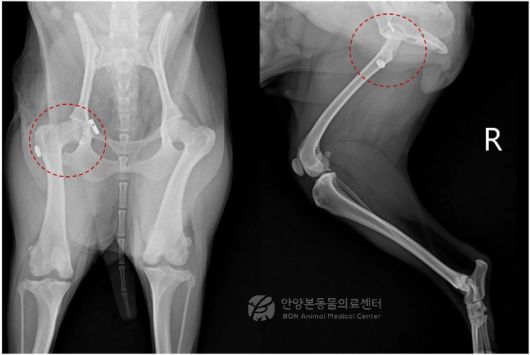

고관절 탈구가 롹인된 반려견의 엑스레이(본동물의료센터 제공) ⓒ 뉴스1 |

추가 방사선 검사 결과, 우측 대퇴골두가 정상적인 관골구 위치에서 이탈해 전방 등 쪽으로 완전히 변위된 상태였다. 외상에 의한 고관절 탈구가 의심됐다. 퇴행성 관절염이나 구조적 손상이 뚜렷하지 않아 의료진은 관절을 최대한 보존하는 방향의 수술적 치료를 결정했다.

수술은 탈구된 고관절을 노출한 뒤 손상된 인대를 정리하고 인공 인대를 설치해 관절을 제자리로 되돌리는 방식으로 진행됐다. 이후 파열된 관절낭을 봉합하고 고관절의 안정성과 가동 범위를 확인한 뒤 수술을 마무리했다. 수술 후 추적 방사선 검사에서도 고관절은 안정적으로 유지되고 있는 것으로 확인됐다.

수술 후 방사선 검사 결과(본동물의료센터 제공) ⓒ 뉴스1 |